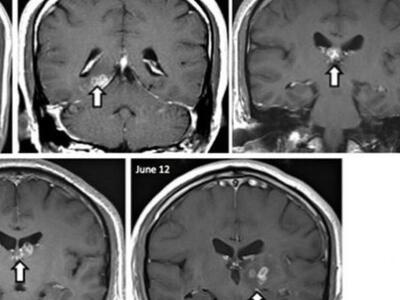

Μάλιστα το σκουλήκι, σύμφωνα με τους επιστήμονες, δεν έμενε ακίνητο στον εγκέφαλο, αλλά έκοβε βόλτες από το ένα ημισφαίριο στο άλλο, σε απόσταση τουλάχιστον πέντε εκατοστών, διασχίζοντας ευαίσθητα κέντρα του εγκεφάλου!

Ένα σκουλήκι-ταινία που ως παράσιτο συνήθως μολύνει σκύλους, γάτες και άλλα ζώα, ανακαλύφθηκε από Βρετανούς γιατρούς μέσα στον εγκέφαλο ενός 50χρονου Κινέζου. Το σκουλήκι, μήκους ενός εκατοστού, ζούσε τουλάχιστον επί τέσσερα χρόνια μέσα στο κεφάλι του άνδρα και του προκαλούσε τρομερούς πονοκεφάλους, επιληπτικές κρίσεις, αλλοίωση της αίσθησης της όσφρησης, ξαφνικές αναλαμπές μνήμης και άλλα νευρολογικά συμπτώματα.

Οι γιατροί σε ένα βρετανικό νοσοκομείο προσπαθούσαν επί χρόνια να καταλάβουν τι προκαλούσε τα συμπτώματα στον άνδρα, αλλά παρ' όλη την πληθώρα των εξετάσεων είχαν αποτύχει να βρουν την αιτία, ώσπου αναγκάστηκαν να καταφύγουν σε εγχείρηση. Εκεί, προς μεγάλη έκπληξή τους, ανακάλυψαν το σκουλήκι θρονιασμένο σε σχήμα κορδέλας στη δεξιά πλευρά του εγκεφάλου.